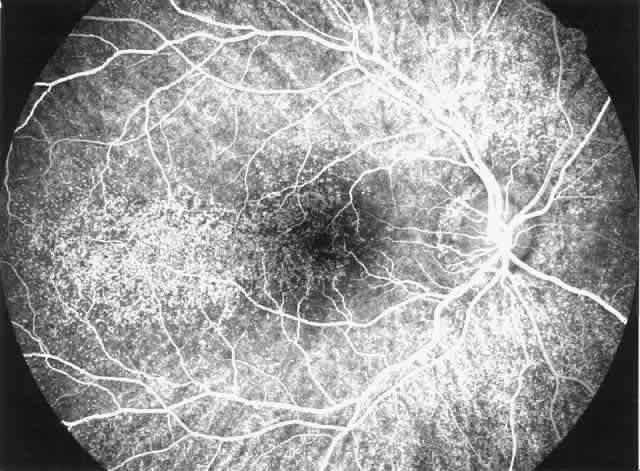

Arterial hypertension is a frequent complication of congenital and acquired renal and renovascular disorders. Arteriolar narrowing, tortuosity, and arteriovenous nicking are common retinal vascular abnormalities in patients with arterial hypertension. In subjects with malignant hypertension, ischemic changes may occur in retina, choroid, and optic nerve and produce cotton-wool spots, flame-shaped hemorrhages, hard exudates, Elschnig's spots, exudative detachment, papilledema, and optic atrophy (Fig. 1). In patients with severe and long-standing hypertension a sudden relative fall in arterial pressure may cause infarction of the optic nerve and blindness. Anterior ischemic optic neuropathy and retinal infarction have been described as complications of hemodialysis-associated hypotension. Uremia, anemia, and papilledema of intracranial hypertension are other risk factors for optic neuropathy in patients with chronic renal diseases.2 In addition, patients with chronic hypertension are predisposed to retinal arterial and venous obstructive diseases leading to visual loss.

Fig. 1. Malignant hypertension with retinal and choroidal vascular manifestations: retinal hemorrhages, exudative retinal detachment, numerous edematous Elschnig's spots (A), and fluorescein angiographic abnormalities with areas of hypoperfusion of the choriocapillaris in the early phase (B), and diffuse leak of fluorescein in the late phase of angiography (C).